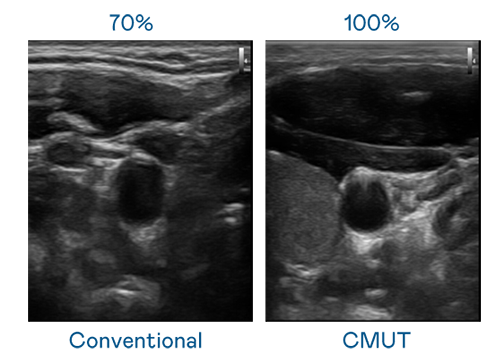

CMUT 技术是一种用电容式微机电元件来产生超音波讯号的技术。与传统 PZT 压电式技术相比,CMUT 频宽增加 30%,更宽频的超音波讯号让影像解析度大幅提升,是实现高影像品质医疗超音波扫描、促进精准医疗发展的关键技术。

超音波影像的解析度高低,首先取决于探头能发出的讯号频宽。九游 CMUT 可提供高清晰的超音波讯号,提供高频宽、高灵敏度、影像纹理细节更高的超音波影像,协助医护人员缩短影像判读时间及利用精准的医疗影像进行诊断。